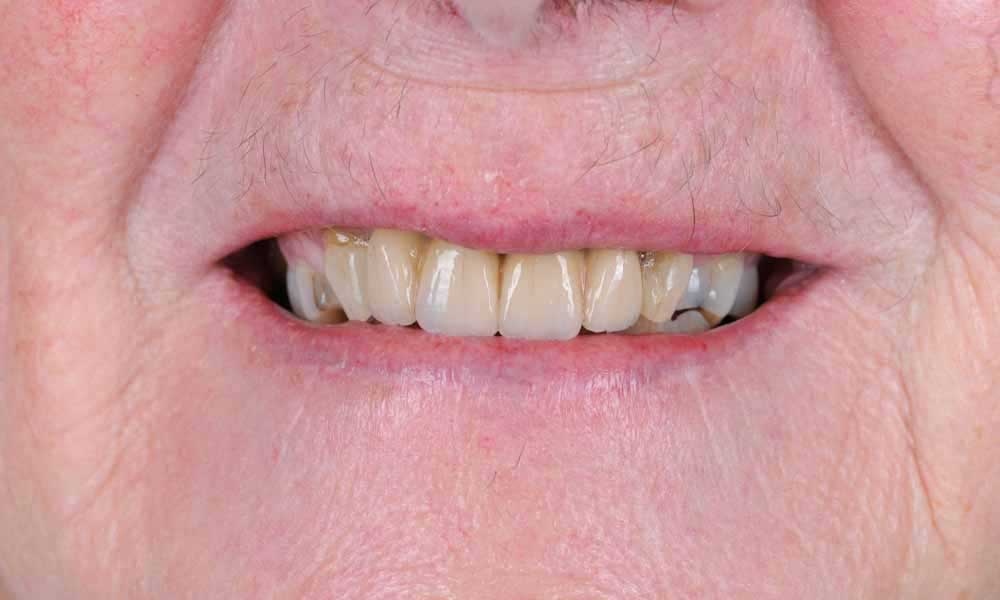

Case Study 2

Missing upper front teeth

Gap restored with 4 unit implant bridge